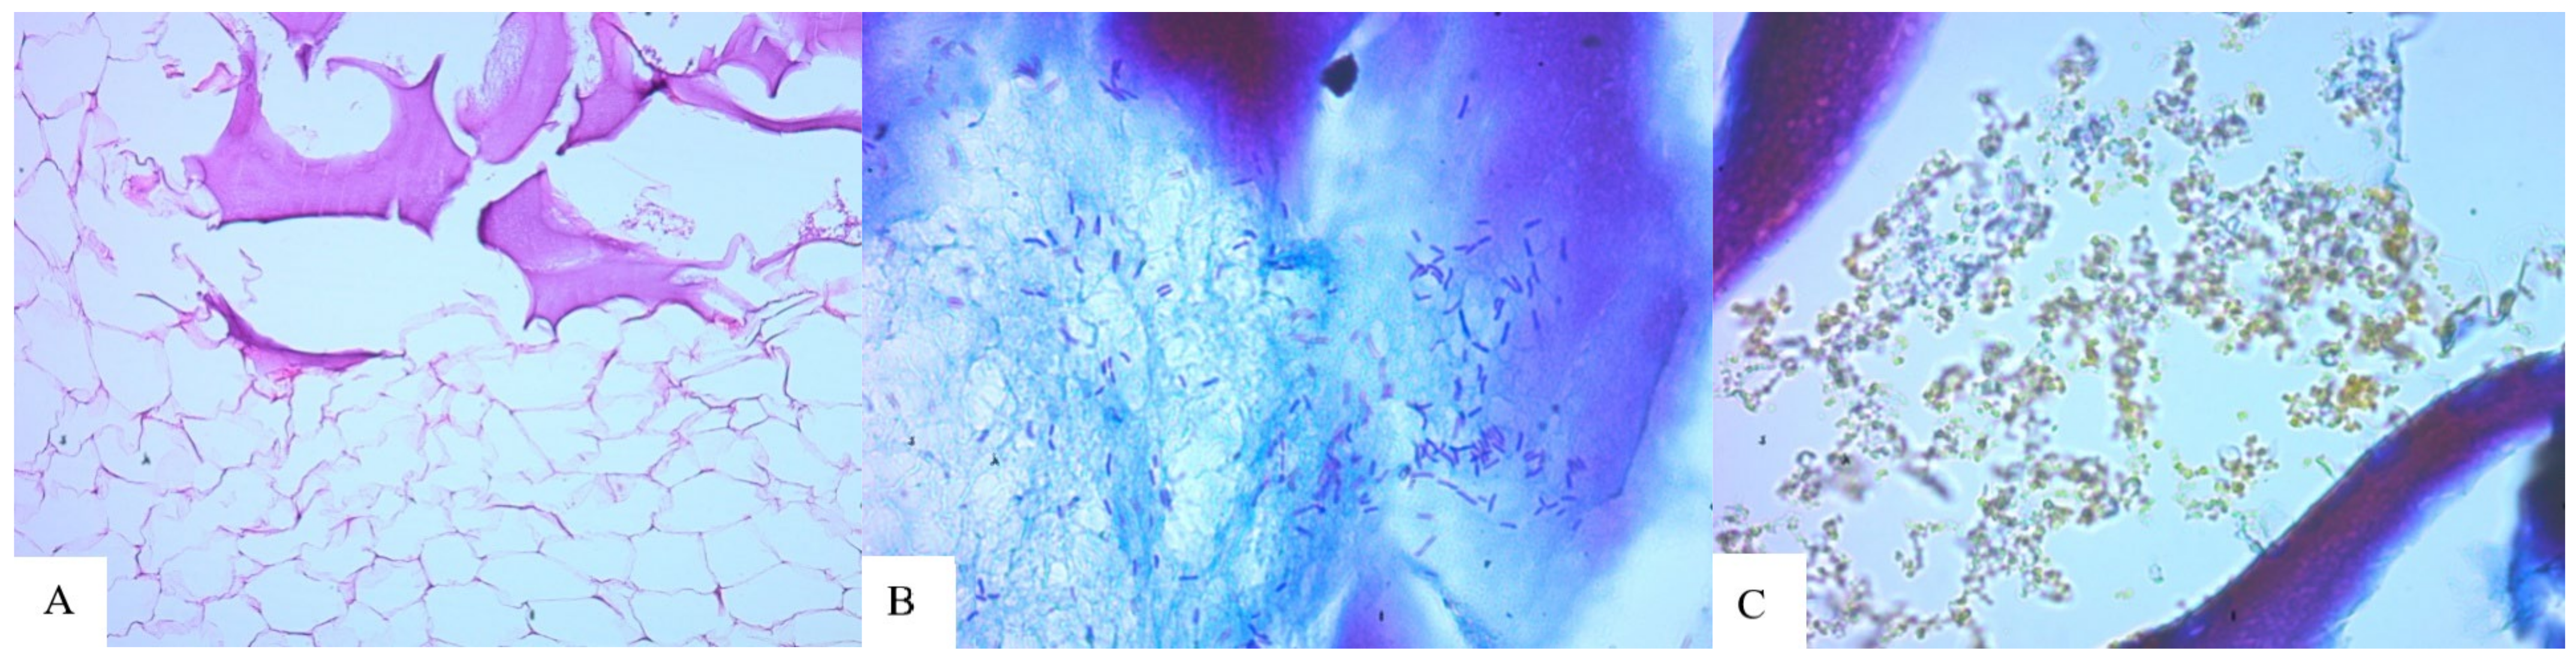

- Foreign substance (gel) migrated in the tissues, provoking the active growth of connective tissue;

- Aseptic and septic inflammatory reactions;

- Sections of round-shaped petrifications with clear contours;

- Lymphoid cell reaction, the presence of voids and necrotic masses, and the formation of cystic cavities;

- Pronounced deformation of adipocytes;

- Muscle tissue with extensive necrosis and effusion of the protein component;

- Numerous mast cells;

- Isolated, giant Pirogov–Langhans cells surrounded by lymphocytes and macrophages.